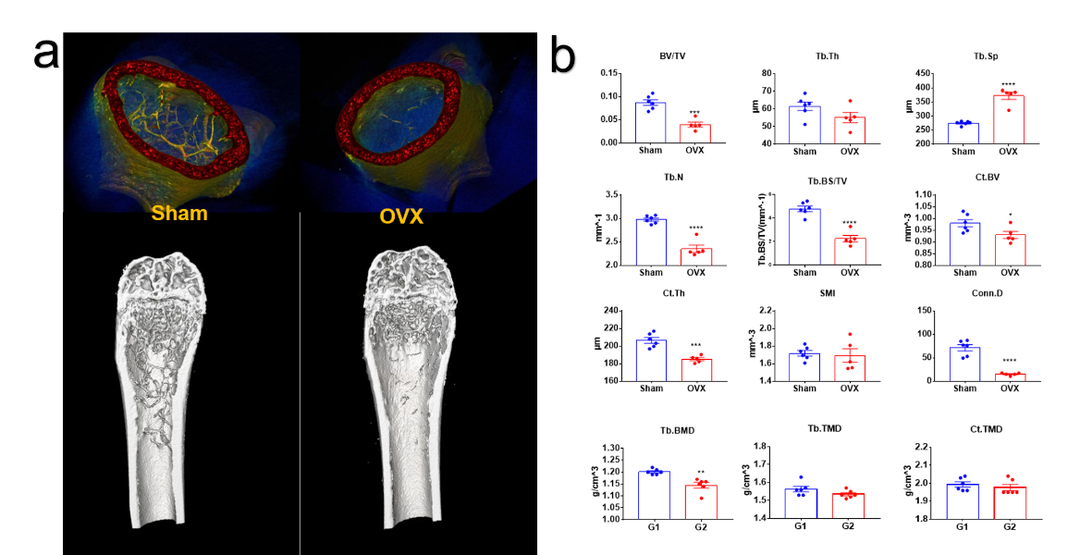

卵巢切除诱导的骨质疏松模型离体检测。(a)骨质疏松模型假手术组(sham)和手术组(OVX)3D重建图像。(b)骨小梁、皮质骨结构性参数以及密度属性参数统计图。指标意义参考下方表格,综上结果模型特征明显,手术成功。

骨分析常见参数的意义